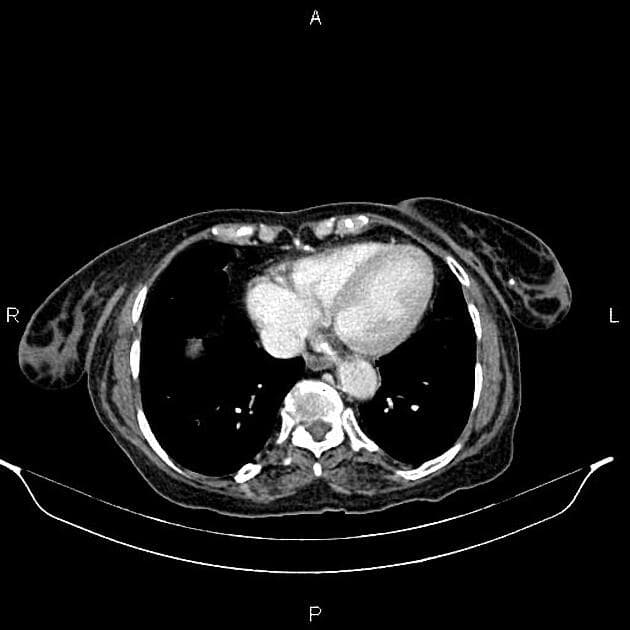

Axial C+ portal venous phase

- Khối tổ chức mềm tăng kích thước 40×28 mm, có ngấm thuốc và một ổ nhỏ vôi hóa, nằm ở đoạn xa niệu quản trái, xâm lấn vào khớp nối niệu quản – bàng quang trái, gây giãn đài bể thận – niệu quản trái nặng và teo nhu mô thận trái.

Khối ở đoạn xa niệu quản; sinh thiết xác định là ung thư tế bào biểu mô niệu quản (urothelial cell carcinoma) gây giãn đài bể thận – niệu quản nặng và teo nhu mô thận (renal parenchymal atrophy).

Ung thư tế bào biểu mô niệu quản đoạn xa (distal ureteral urothelial cell carcinoma)